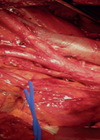

Retroperitoneal sepsis

Case 1 An 80-year-old woman presented with history of recurrent and recent cystitis, low grade pyrexia, abdominal and back pain, and pain on movement of the left hip which was observed to be flexed and externally rotated. What is the...